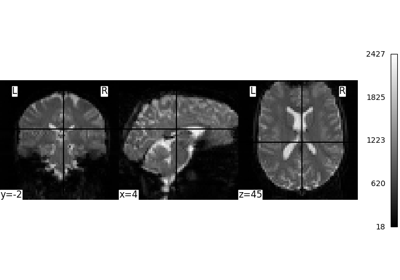

Exercise: Varying the amount of smoothing in an image

Compute the mean EPI for one individual of the brain development dataset downloaded with nilearn.datasets.fetch_development_fmri and smooth it with an FWHM varying from 0mm to 20mm in increments of 5mm

Intermediate steps:

1. Run nilearn.datasets.fetch_development_fmri and inspect the .keys() of the returned object

2. Check the nilearn.image module in the documentation to find a function to compute the mean of a 4D image

3. Check the nilearn.image module again to find a function which smoothes images

4. Plot the computed image for each smoothing value

A solution can be found here.